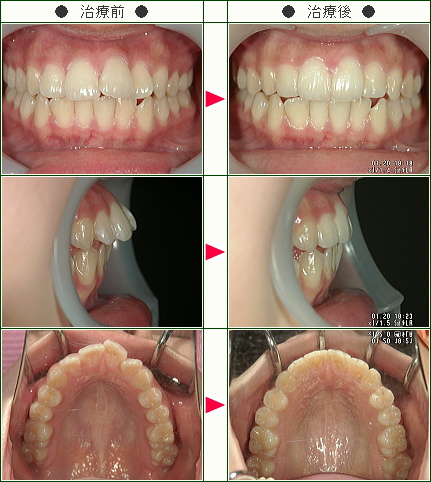

☆出っ歯矯正症例(moe様 19歳 女性)

治療解説

主訴は右上の前歯の前突感の改善です。

まずはワイヤーを使用して右上のデコボコを改善していきます。

ワイヤーの使用期間が約3か月で、マウスピースを3か月使用して歯並びを内側に傾斜して治療していきました。

トータルでの治療期間は6ヵ月で、調整料金を含めたトータルの治療費は29万円です。

歯並びの段差を改善した後に、前歯を内側に入れていくこともおおよそワイヤーで行い、期間短縮をしています。

上側だけの部分矯正では、噛み合わせは変わりませんので、見た目の改善だけの審美治療になります。

部分矯正において、ワイヤーでデコボコを改善するだけだと、矯正前よりも少しだけ前方に出てしまうため、歯の隣接面を少し削ることで前歯の前突感を改善していきます。

どこまで前歯を中に入れたいかで、隣接面を削る量は患者様の判断で決まります。

歯を削らないでデコボコを治すだけですと、デコボコのある上の左右の1番目と上の2番目の間にブラックトライアングルという隙間が残るために、ブラックトライアングルを減らすためにもその部分の隣接面を削ってブラックトライアングルを改善していきます。